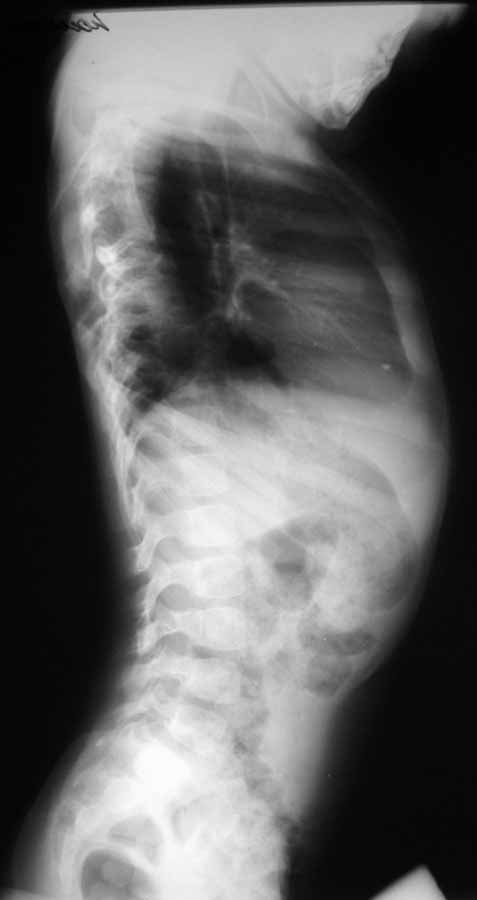

Уважаемые коллеги!Выскажите, пожалуйста, мнения о тактике лечения данной

пациентки.Девочка, 5 лет.ДЗ: Врожденный S образный сколиоз, аномалия развития

позвоночника: клиновидные 5 6 грудные позвонки, аномалия развития грудной клетки:

деформация ребер. Анамнез заболевания: Болеет с рождения, начала ходить в 1,5 года. В 5

месяцев мама отметила наличие реберного горба, который увеличивался в размерах, в 1год 10

месяцев произведена рентгенография позвоночника отмечена его деформация. Заранее